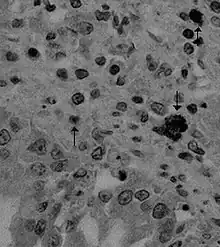

Canine coronavirus antigen (arrows) in canine lung tissue